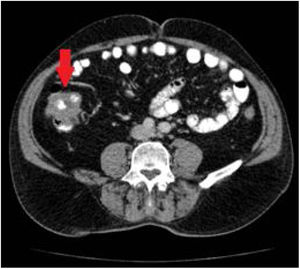

Ante estos hallazgos, se realizó estudio de extensión con TC toracoabdominal, en el que se describió en el colon ascendente, hacia el ángulo hepático, un engrosamiento asimétrico en un segmento aproximado de 8cm, con probable afectación de la válvula ileocecal, compatible con neoplasia primaria sin adenopatías, enfermedad a distancia ni signos de obstrucción intestinal (fig. 2).